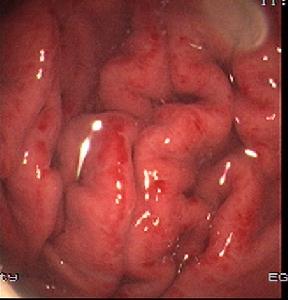

病理改變

病變可為瀰漫性,或僅限於胃竇部黏膜的卡他性炎症。黏膜充血水腫,表面有滲出物及粘液覆蓋,可有點狀出血和不同程度的糜爛。

因有膜有淋巴細胞、中性粒細胞、漿細胞及少數嗜酸粒細胞浸潤、水腫、黏膜血管充血,偶有小的間質性出血,嚴重者黏膜下層水腫、充血。